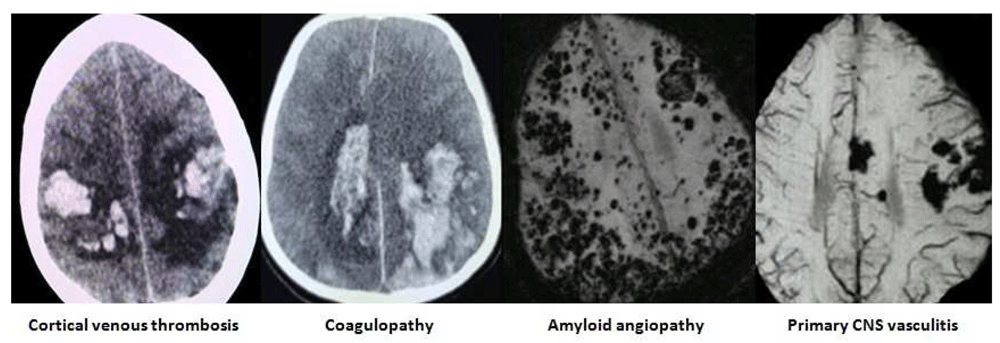

The images of the varied etiological causes of SMICH are demonstrated in the Figure 1–Figure 3.

All images are original, deidentified, and of our patients themselves.

Hypertensive angiopathy and cerebral amyloid angiopathy accounted for more than 50% of cases in SMICH (Wu TY et al.) (Renard et al., 2020) (Stemer et al., 2010). They accounted for only 42.5% of the SMICH in our study. In total, 75% of our patients presenting with SMICH had a history of hypertension and were hypertensive on presentation. Paradoxically, 97.5% of diagnosed cases of hypertension lacked compliance to their medications.

The pathophysiology of SMICH was proposed to be due to degenerative alterations in the intraparenchymal arterioles caused by long-term, uncontrolled hypertension and the simultaneous rupture of bilateral charcot-bouchard microaneurysms (Yen et al., 2005). As per the “biphasic hypothetical mechanism," an initial ictal hematoma causes an adrenaline spike that disrupts the cerebral autoregulation thereby harbingering the rupture of already weakened arterioles (Yen et al., 2005). Primary SMICH characteristically showed high microhemorrhages burden of varying age in MRI studies. This also highlights the probable role of auto-regulatory dysfunction following the ictal bleed as the prime pathological genesis behind the SMICH (Stemer et al., 2010).